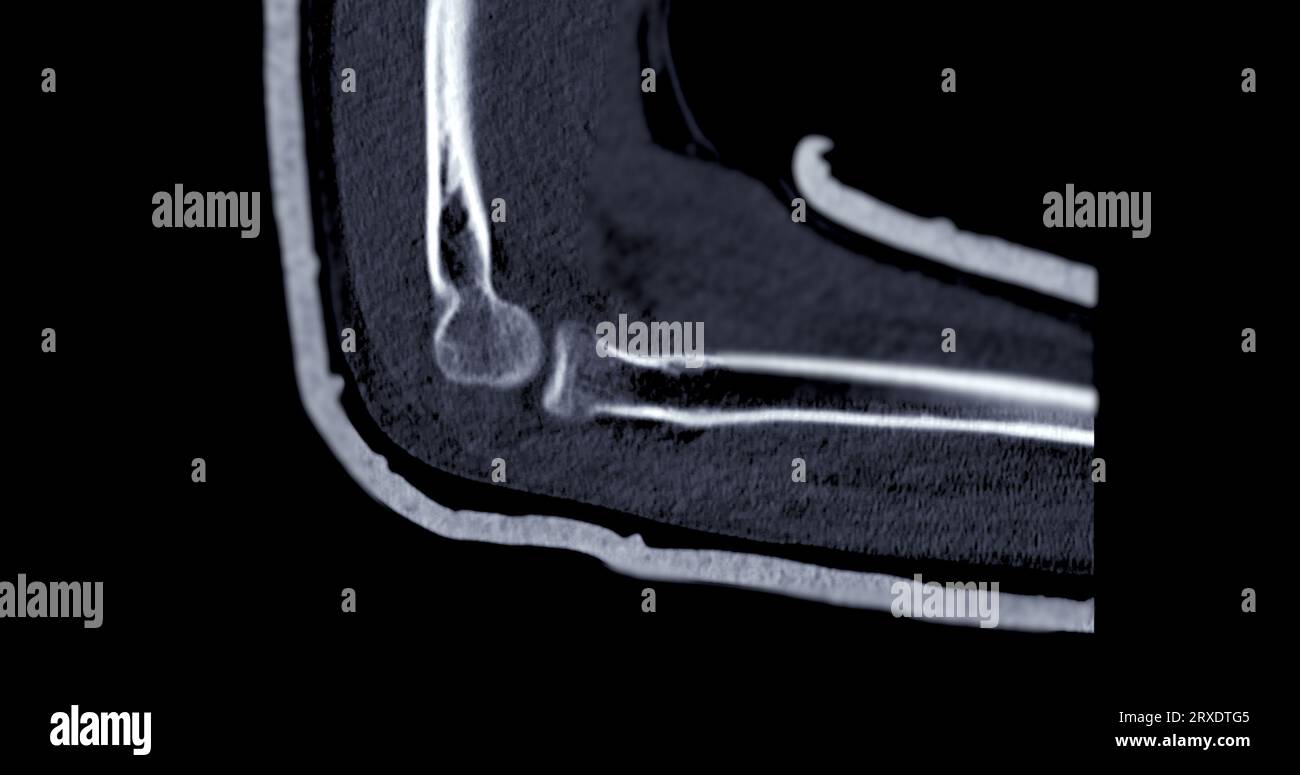

From www.alamy.com

CT scan of elbow joint sagittal view Stock Photo Alamy Elbow Arthritis Ct Multiple osteophytes and joint space narrowing are observed. Elbow arthritis is an uncommon condition that can cause debilitating pain, stiffness, or instability. The most common etiologies include rheumatoid arthritis, posttraumatic. Osteomyelitis/septic arthritis of the elbow: Advanced diagnostic imaging, such as a computed tomography (ct) scan or magnetic resonance imaging (mri) scan, is typically not needed to diagnose osteoarthritis of the. Elbow Arthritis Ct.